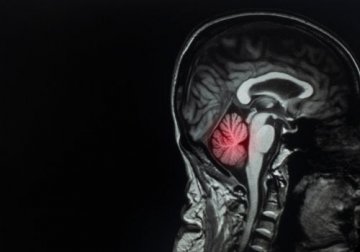

Metastasi cerebrale: definizione, cause e trattamento

La metastasi cerebrale è il tumore cerebrale più frequente e rappresenta una vera sfida per i medici. Costituisce, infatti, circa il 90% dei casi di tumore al cervello.

Si stima che tra il 10 e il 40% dei malati di cancro sviluppi metastasi cerebrali. L’incidenza è in aumento per via della maggiore sopravvivenza media grazie alle terapie attuali.